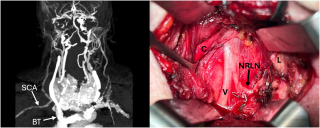

Case presentation

A 31-year-old previously healthy woman, with no surgical history, presented with sudden-onset, severe peri-umbilical abdominal pain unresponsive to high-dose opioids. CT-scan revealed mildly dilated distal jejunum with mesenteric edema and free fluid (Fig. 1, 2). Because of persistent pain despite step III analgesia, emergency diagnostic laparoscopy was performed. Intraoperatively, a closed-loop obstruction of an ileal segment was identified, herniated through a narrow internal window formed by an adherent mesenteric vessel supplying a Meckel’s diverticulum (Fig. 3). The vascular band was divided, releasing the closed loop, with no irreversible small bowel ischemic damage. The Meckel’s diverticulum was resected. The post-operative course was uneventful, and the patient was discharged after two days.